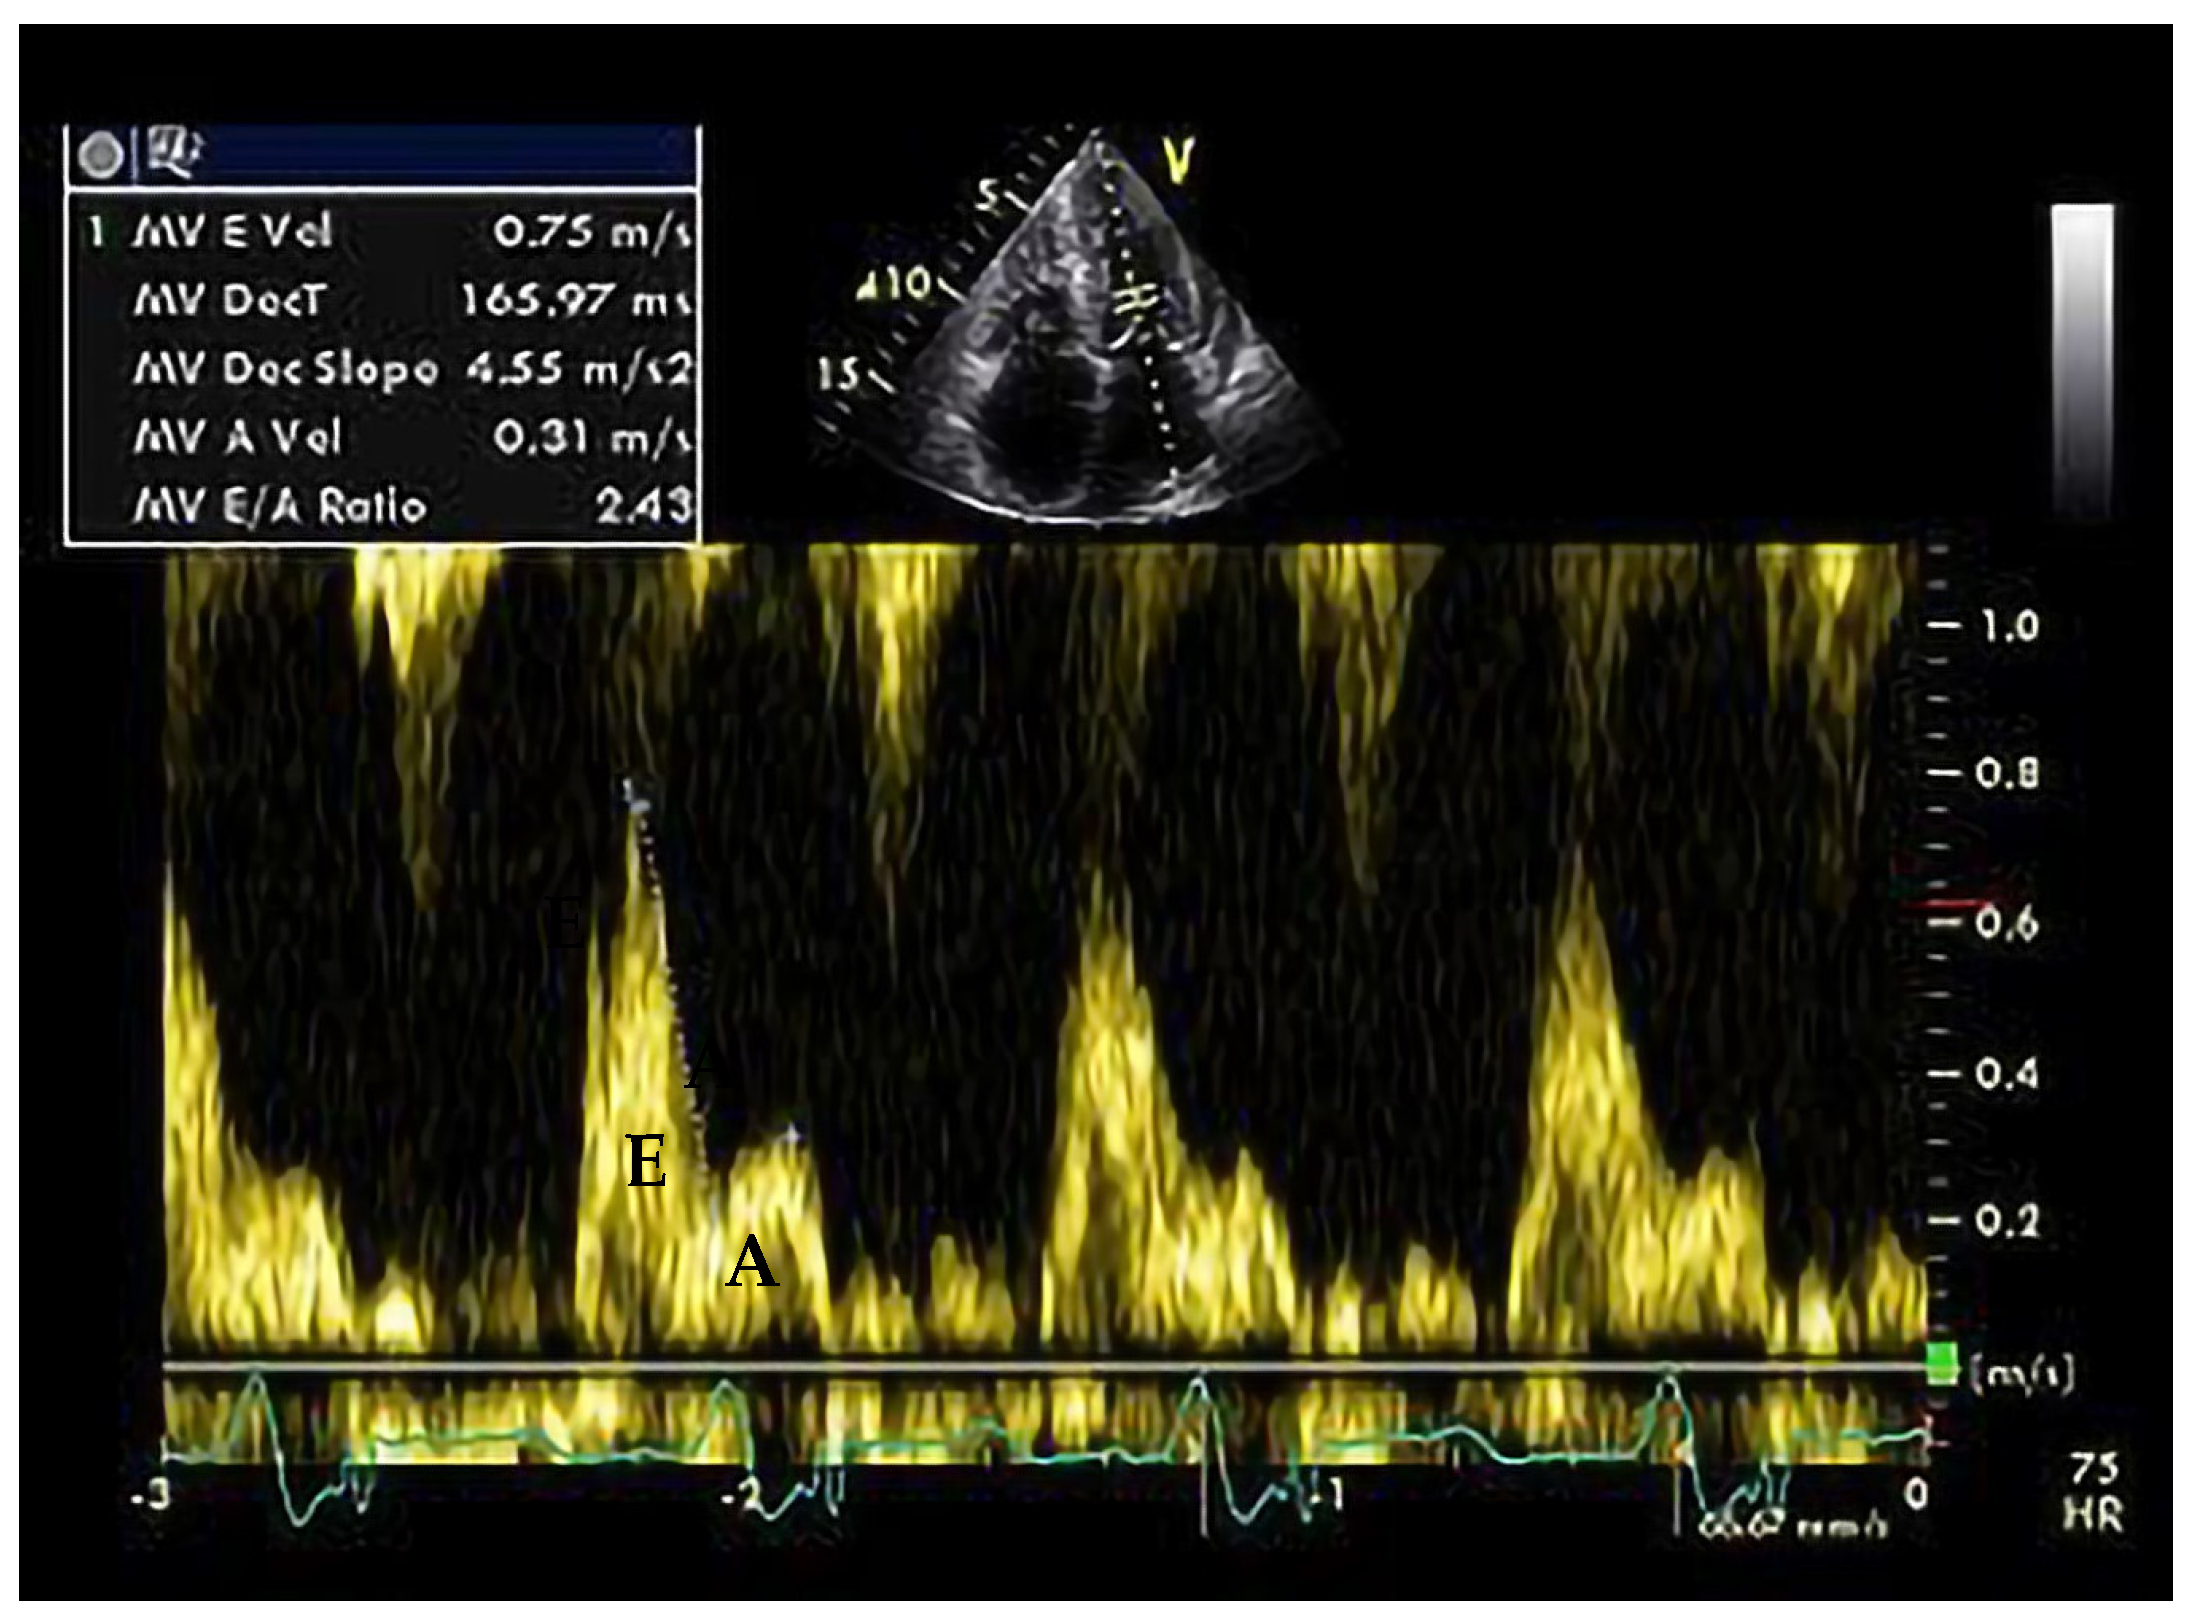

4. Hypertrophic Cardiomyopathy